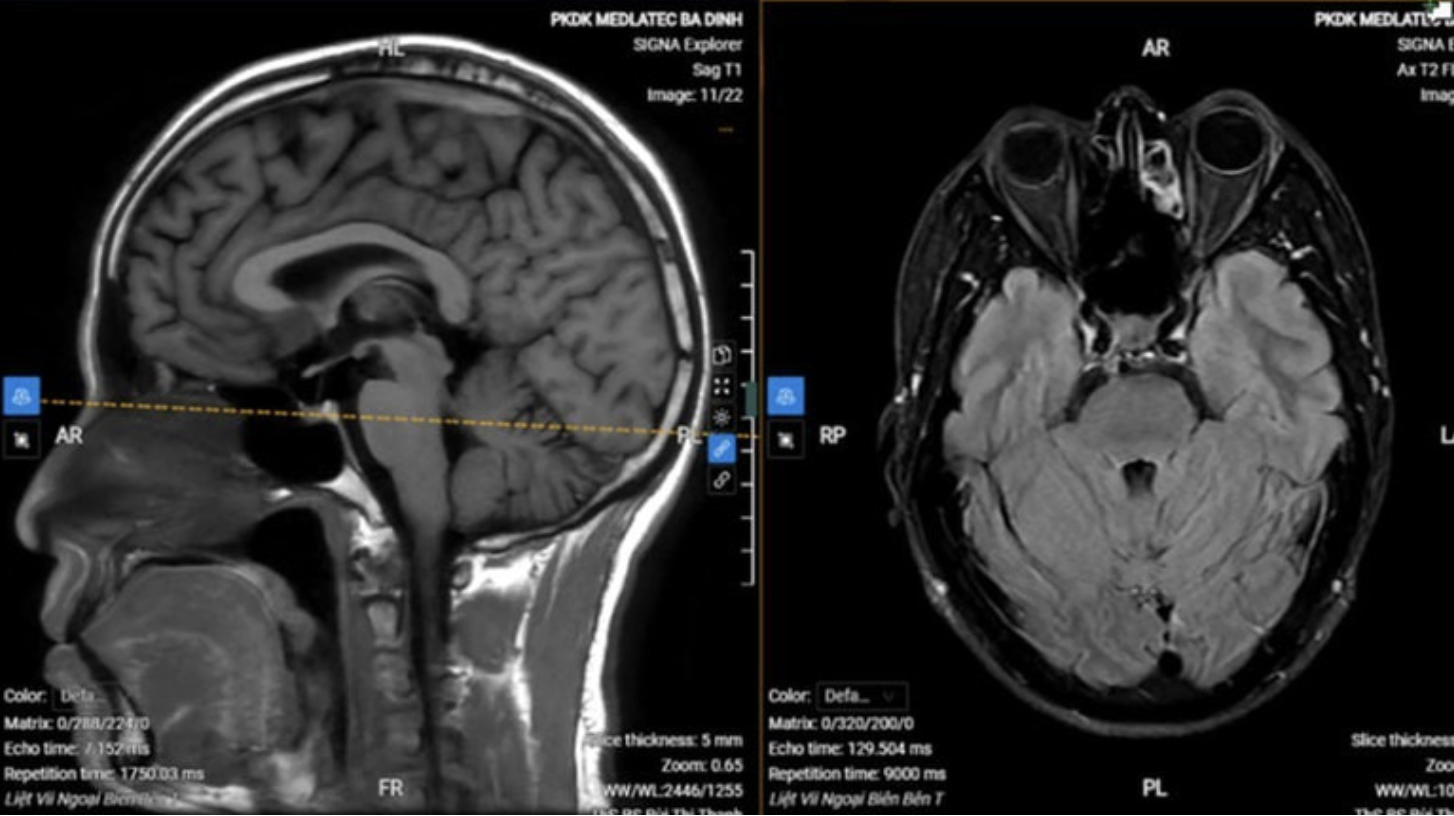

Không chỉ hô hấp, mùa lạnh cũng là thời điểm các vấn đề thần kinh ngoại biên xuất hiện nhiều hơn. Bệnh viện đa khoa Medlatec vừa ghi nhận trường hợp nam bệnh nhân 45 tuổi đến khám vì tê bì nửa mặt trái. Thăm khám cho thấy dấu hiệu liệt dây thần kinh mặt: méo miệng, mờ nếp nhăn vùng má, khó nhắm kín mắt, kèm tê bì. Chụp MRI không ghi nhận tổn thương cấp tính nội sọ. Bệnh nhân được chẩn đoán liệt dây thần kinh số VII ngoại biên vô căn (liệt Bell) và điều trị ngoại trú kết hợp tập cơ mặt, chăm sóc mắt, phối hợp châm cứu theo hướng dẫn.

Hình ảnh chụp MRI của bệnh nhân.

Theo bác sĩ chuyên khoa Thần kinh, liệt dây VII là bệnh khá phổ biến, hay gặp vào mùa đông – xuân. Nguyên nhân có thể liên quan nhiễm trùng, chấn thương, khối u… nhưng yếu tố lạnh được ghi nhận là một tác nhân thường gặp. Dây thần kinh số VII liên quan vận động cơ mặt, cảm giác và vị giác, nên khi bị ảnh hưởng người bệnh có thể khô mắt do giảm tiết, nhắm mắt không kín, ăn nhai dễ đọng thức ăn một bên, miệng kéo lệch, đau vùng góc hàm – thái dương – tai, thay đổi vị giác, nhạy cảm âm thanh.